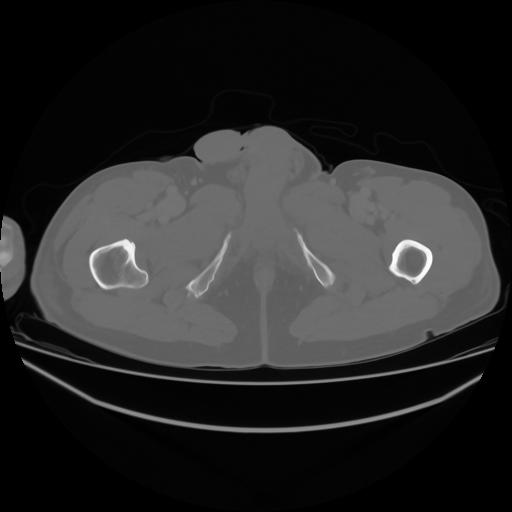

4 CUERPO,CE,Axial,3.0,CUERPO,,